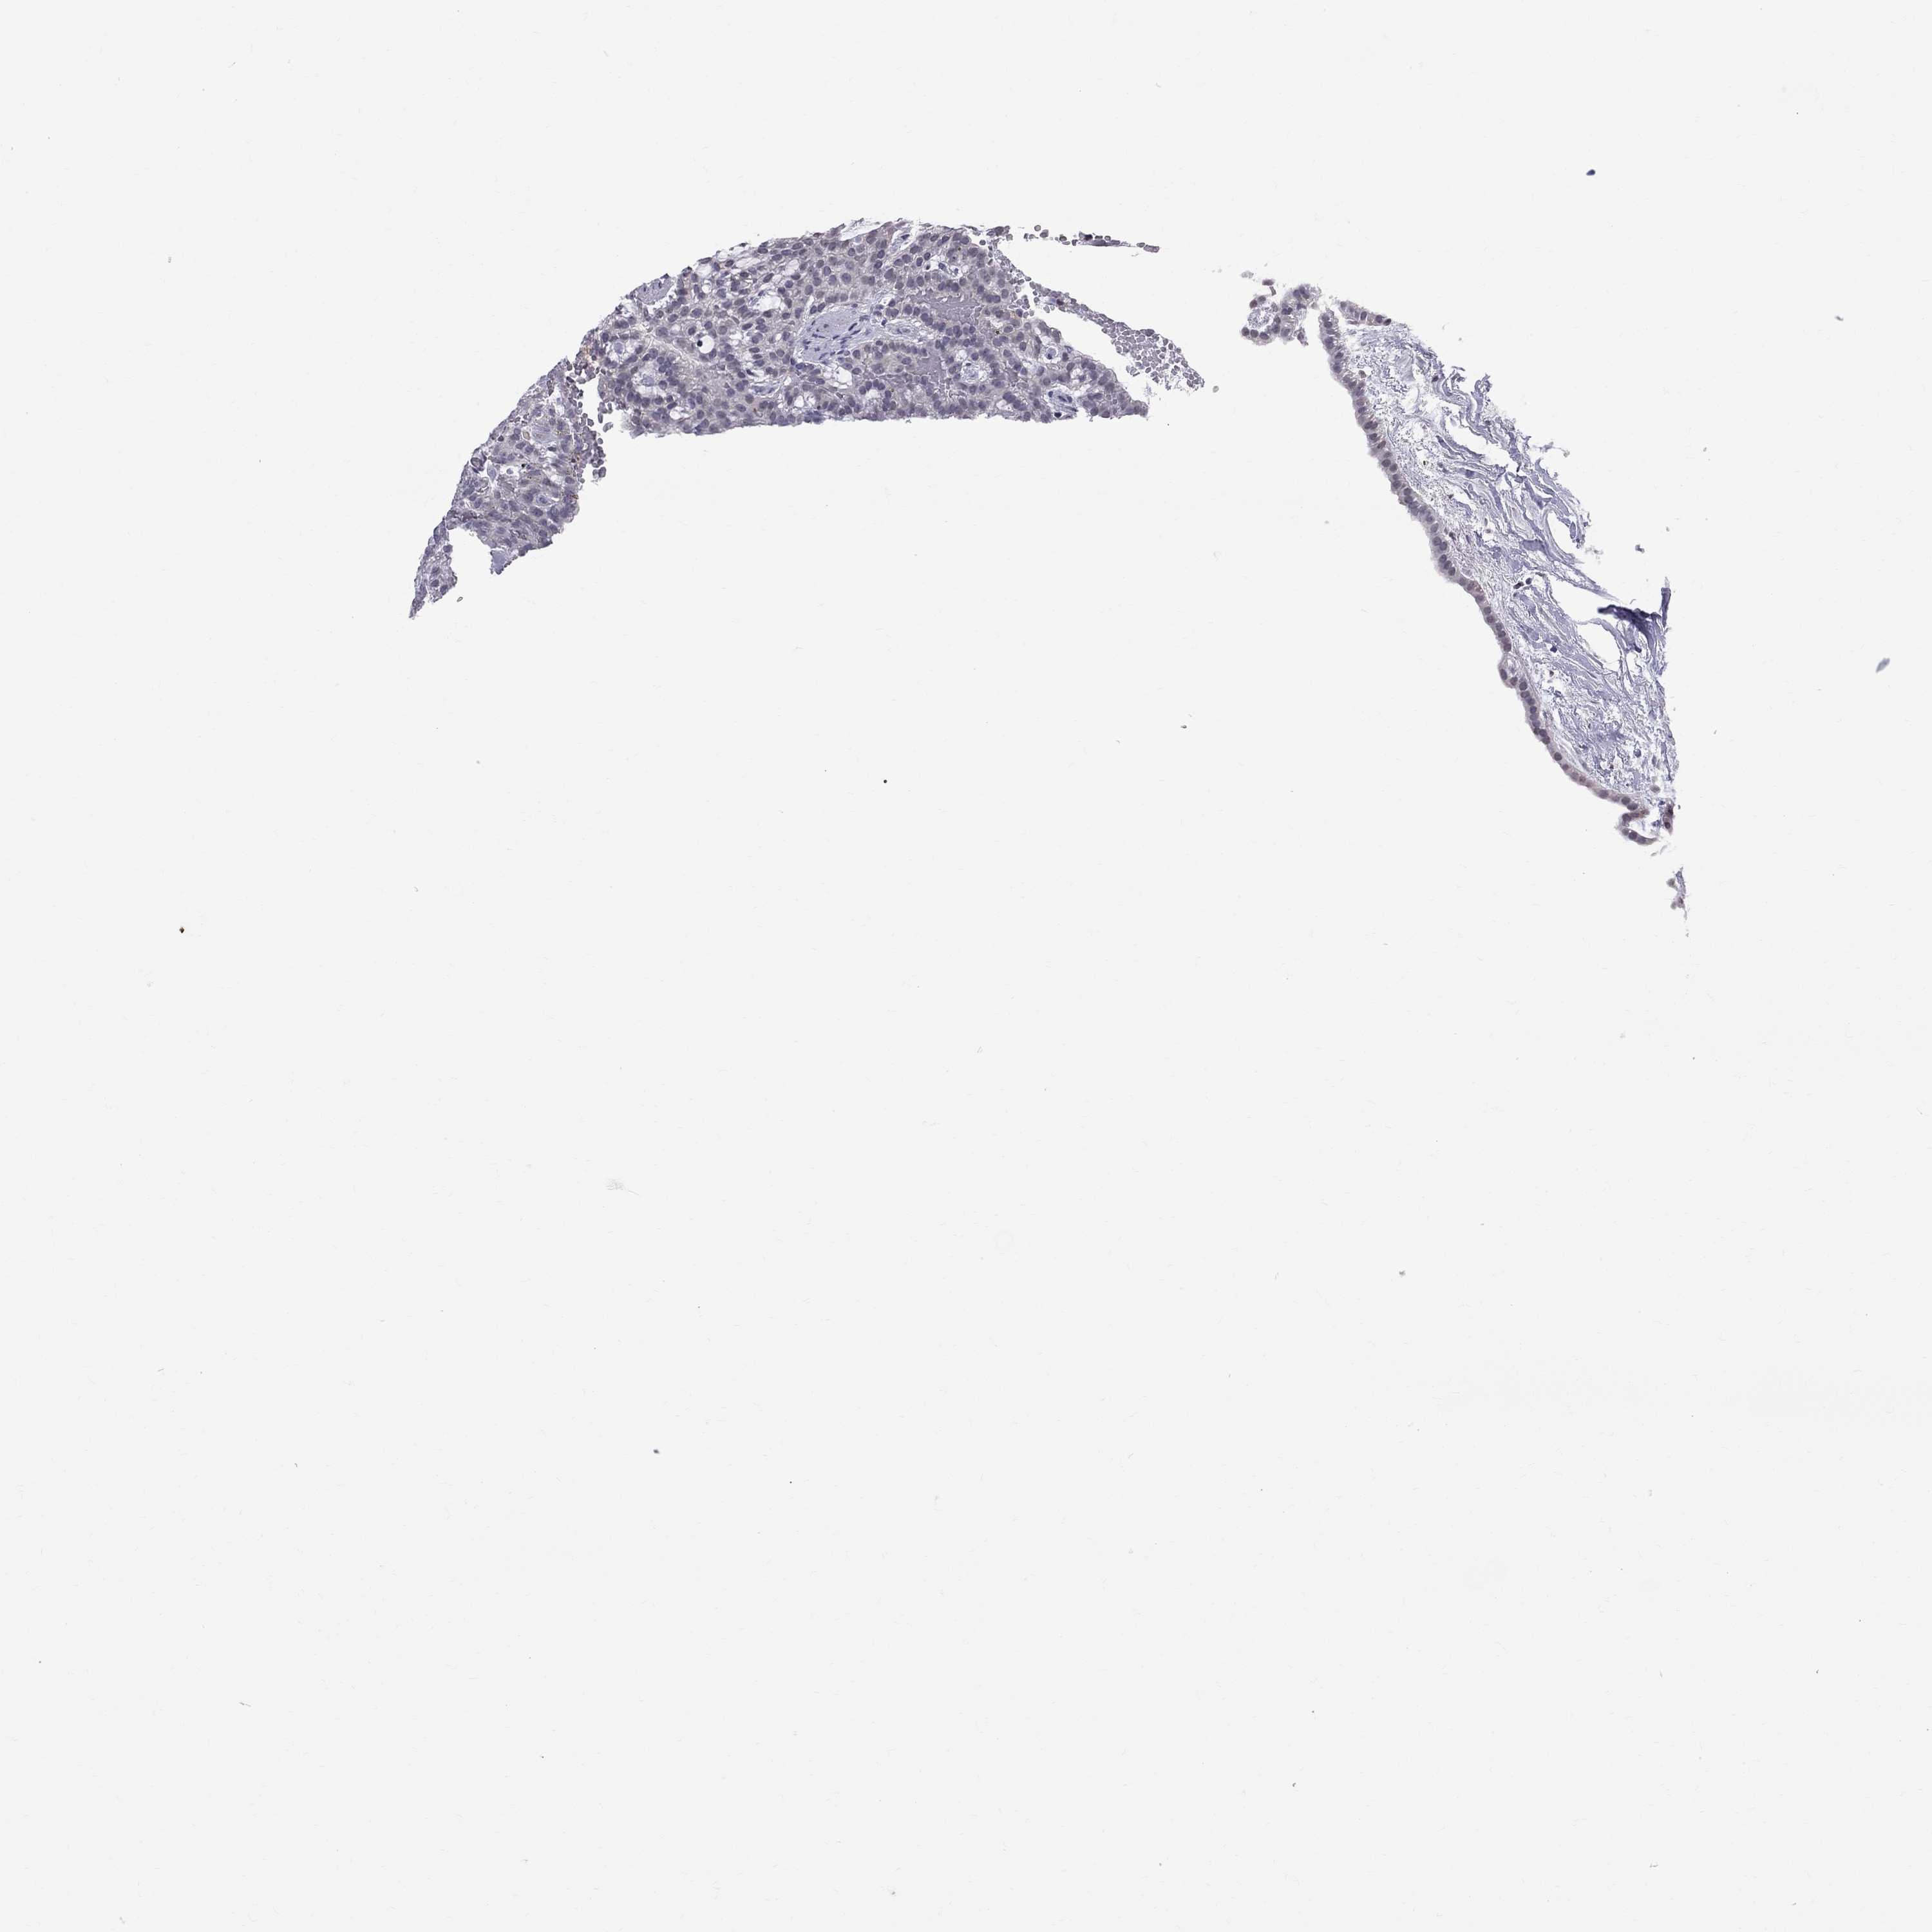

KIDNEY RENAL CLEAR CELL CARCINOMA (VALIDATION) - Interactive survival scatter ploti

The Survival Scatter plot shows the clinical status (i.e. dead or alive) for all individuals in the patient cohort, based on the same data that underlies the corresponding Kaplan-Meier plots. Patients that are alive at last time for follow-up are shown in blue and patients who have died during the study are shown in red.

The x-axis shows the expression levels (FPKM) of the investigated gene in the tumor tissue at the time of diagnosis. The y-axis shows the follow-up time after diagnosis (years). Both axes are complimented with kernel density curves demonstrating the data density over the axes. The top density plot shows the expression levels (FPKM) distribution among dead (red) and alive patients (blue). The right density plot shows the data density of the survived years of dead patients with high and low expression levels respectively, stratified using the cutoff indicated by the vertical dashed line through the Survival Scatter plot. This cutoff is automatically defined based on the FPKM cutoff that minimizes the p-score. The cutoff can be changed by dragging the vertical line or by entering a cutoff value in the square labeled "Current cut-off".

Under the Survival Scatter plot the p-score landscape (black curve; left axis) is shown together with dead median separation (red curve; right axis). Dead median separation is the difference in median mRNA expression between patients who have died with high and low expression, respectively. It is calculated as follows: median FPKM expression of dead patients with high expression - median FPKM expression of dead patients with low expression. This is intended to aid the user in visually exploring custom cutoffs and the associated p-scores and dead median separation.

Individual patient data is displayed and can be filtered by clicking on one or more of the category buttons on the top of the page. Categories describing expression level and patient information include: high, low, alive, dead, female, male and tumor stages. The scale of the x-axis can be toggled between linear and log-scale by clicking on the "x log" button. Mouse-over function shows TCGA ID, patient information and mRNA expression (FPKM) for each patient.

& Survival analysisi

Kaplan-Meier plots summarize results from analysis of correlation between mRNA expression level and patient survival. Patients were divided based on level of expression into one of the two groups "low" (under cut off) or "high" (over cut off). X-axis shows time for survival (years) and y-axis shows the probability of survival, where 1.0 corresponds to 100 percent.

MUC15 is not prognostic in Kidney Renal Clear Cell Carcinoma (validation)

TCGA RNA samplesi

RNA-seq data is reported as average FPKM (number Fragments Per Kilobase of exon per Million reads), generated by the The Cancer Genome Atlas (TCGA) .

Normal distribution across the dataset is visualized with box plots, shown as median and 25th and 75th percentiles. Points are displayed as outliers if they are above or below 1.5 times the interquartile range. FPKM values of the individual samples are presented next to the box plot.

Average pTPM 0.2

Number of samples 100